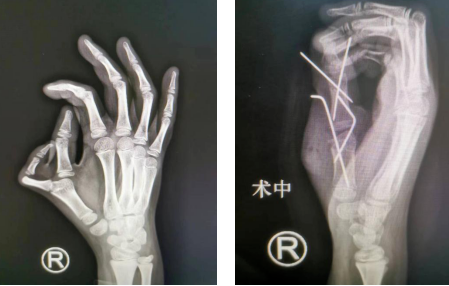

前不久,我院小儿骨科收治1名9岁双侧拇指多指畸形患儿,患儿左手拇指多指畸形II型,右手VII型。李甲主任、李海建、王大伟医生手术团队先为患儿做了“右拇指多指切除截骨矫形内固定肌腱韧带重建带蒂皮瓣修复术”,手术很成功。

术前外观(左图)术后即刻(右图)

术前(左图)术后即刻(右图)

术前组织手术方案讨论,李甲主任考虑,患儿主拇指近节、远节均偏斜,需要截骨矫形。手术操作首先需要切开皮肤、皮下,切除多余骨骼并彻底切除异常形态骨骺,保留侧副韧带、肌腱、部分皮肤组织瓣。